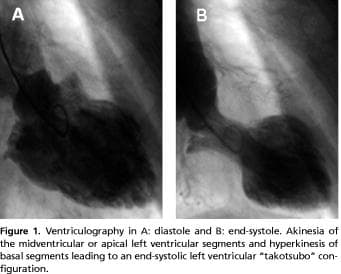

Four patients with a suspected acute myocardial infarction had coronary angiography performed ≤ 12 hours after symptom onset. The remaining three patients underwent coronary angiography within 24 hours, three and 11 days after the onset, respectively. No obstructive coronary disease was identified in any of the patients. The delay in the first case was due to an attempt of haemodynamic stabilizing the patient with inotropic agents at the local hospital. In the second case the patient was initially hospitalized for surgery because of a fracture of the hip, and subsequently transferred for coronary angiography because of ECG changes. An 81 year-old woman was admitted with pneumonia, and due to continued chest pain a coronary angiography was performed on the eleventh day. Three patients had normal coronary arteries, three had mild luminal irregularities and one had a non-significant stenosis distally in the ramus descendens anterior. Ventriculography was performed in four patients (Figure 1).

All patients had echocardiography performed during hospital stay. In three patients in whom ventriculography was not performed, LV apical ballooning was assessed by echocardiography. During the acute phase, all patients had mid-ventricular dysfunction and apical hypokinesis or akinesia. A transient dynamic intra-ventricular pressure gradient of 33 mmHg was demonstrated in one patient. This gradient had disappeared at follow-up echocardiography eight weeks later. Left ventricular systolic function was normalized at follow-up in all patients (Table 1).